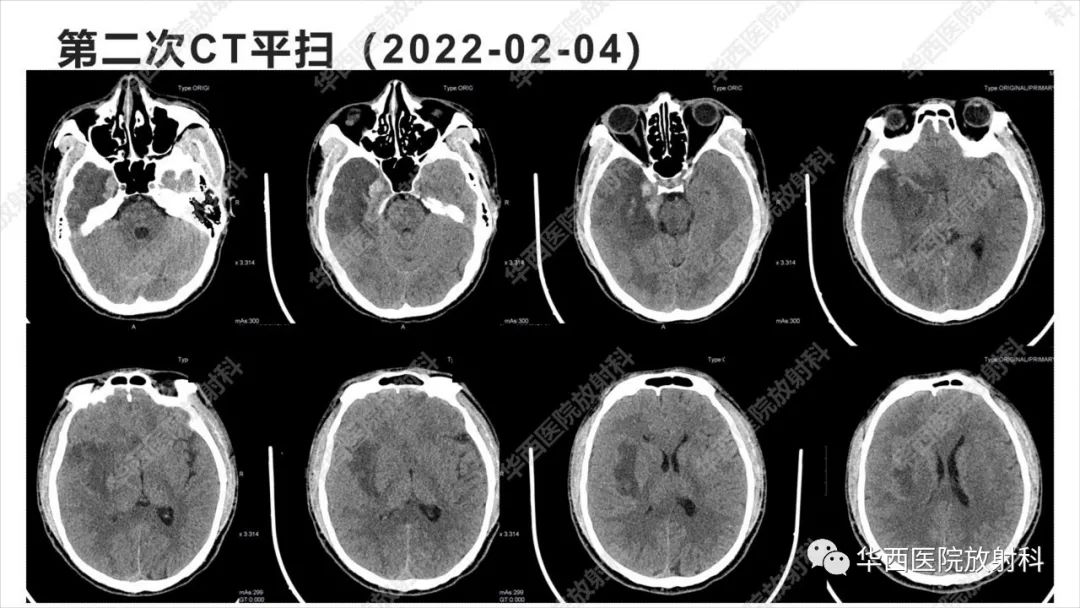

【病例】出血坏死性病毒脑膜脑炎1例CT及MR影像学表现和鉴别诊断-3